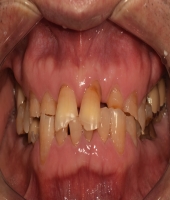

| ● 진료과목 : [임플란트] 치주환자의 임플란트 보철치료

| ● 내용 : 50대 치주환자의 임플란트치료. |